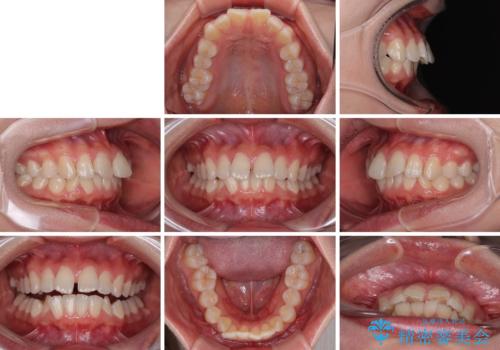

深い咬み合わせによる隙間 インビザライン矯正でコンプレックスを改善

- 上の前歯の隙間を気にして来院された患者様です。

インビザラインにより、上下の歯列を側方に拡大しつつ、前歯の隙間を閉じていくこととしました。

隙間の原因は強い咬合力や舌の突出癖、小帯の異常付着などがありますが、舌のトレーニングをしっかりと行いながら、装着時間を遵守して装着していただいたおかげで、スムーズに治療を終えることができました。